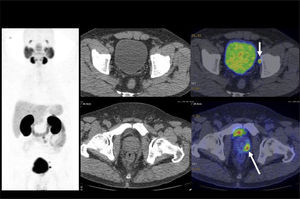

El PET/CT utilizando F18-FDG, dado la excreción fisiológica por vías urinarias del radiotrazador, no es propicio para la evaluación de los tumores primarios (16). Cuando los tumores muestran similar captación de F18-FDG que el contenido urinario, pueden no ser visibles salvo en las imágenes de TC (15). En cambio, si el tumor es más captante que la orina (Figura 3), o menos (Figura 4), puede ser detectado realizando un adecuado ventaneo de la imagen del PET.

El contraste fisiológico de las vías urinarias no es un problema respecto a la detección de compromiso ganglionar y a distancia, que representa el verdadero aporte del PET/CT en estos pacientes, al detectar pequeños ganglios que no constituyen adenopatías en el UroTAC (Figuras 4 y 5), y pesquisar siembra secundaria a distancia con mayor sensibilidad que las técnicas convencionales (17).